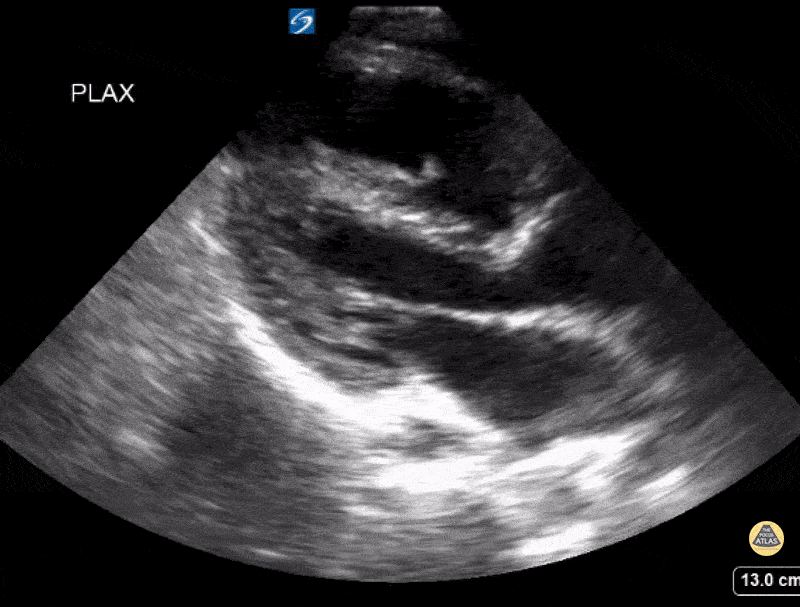

PLAX view of patient with Tetralogy of Fallot with pulmonary atresia demonstrating a moderately dilated and hypertrophied right ventricle. Contributor: Kathryn Pade, MD